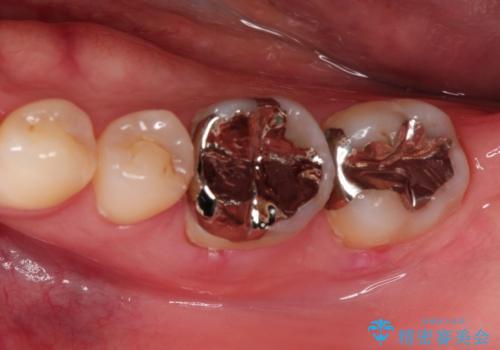

【根管治療】噛んだ時にしみる。最近になってズキズキ痛み、長引く痛みがある

担当医 河口智英